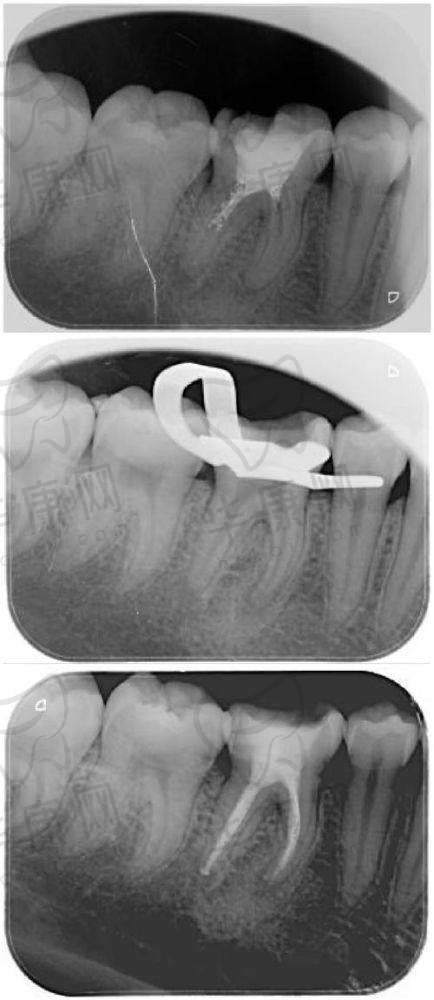

有许多孩子在美植口腔接受了儿童根管治疗,取得了良好的成效。比如,有一位小朋友因为龋齿导致牙髓炎,疼痛难忍。在美植口腔,医生为他进行了根管治疗。治疗后,小朋友的疼痛症状消失,牙齿修复了正常的功能。

美植口腔的根管治疗不仅解决了孩子们的牙齿疼痛问题,还能有效地保留患牙,促进牙齿的正常发育。通过定期的回访和复查,医生可以及时了解治疗成效,确保孩子们的口腔健康。